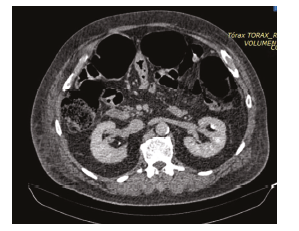

Both patients presented with large abdominal distention, bloating, and constipation. One patient developed a confusional state with hypoactive delirium. Both presented with gastric residuals. Intra-abdominal pressure (IAP) results showed hypertensive values in 1 patient and abdominal compartment syndrome in the other patient. Both required vasopressors to achieve an abdominal perfusion pressure of >60 mm Hg. Laboratory investigations showed hyperleukocytosis, elevated C-reactive protein, and kidney injury (Kidney Disease Improving Global Outcomes [KDIGO] score of 1). Abdominal radiographies showed large distention of the colon. Abdomen tomographies showed dilation of the colon, but there was no evidence of any obstruction or edema of the wall of the colon (Figure 1). The diameter of the cecum was 11 cm in 1 patient and 9 cm in the other (Figure 2). Rectal examinations did not reveal any matter inside. Intravenous neostigmine treatment was started at a dose of 2.5 mg, with both patients requiring continuous infusion at 0.3 mg/hour, which was maintained for an average of 16 hours, achieving reinstatement of the intestinal transit.

Figure 1. Abdominal Computed Tomography Scan Showing Great Distention of the Colon